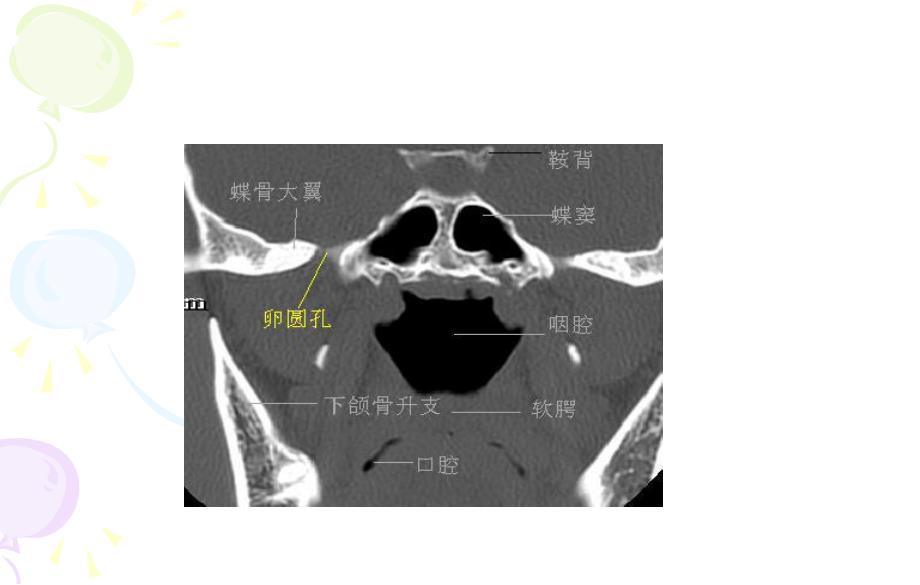

1、鼻窦病变总结鼻窦病变总结鼻窦的正常解剖CT号:056768 姓名:韩东莲 性别:女年龄:73岁 病历号:408752 病史:患者间断流涕、鼻塞6年,左侧牙痛、面部疼痛20天,平日间断感冒,体质相对弱。城关医院CT示:左侧鼻窦炎、上颌窦骨壁不 光滑,有破坏迹象。汾阳医院CT:左侧上颌窦高密度病变,考虑 黏液囊肿,建议增强扫描除外恶性病变 2012.12.08出院诊断:慢性鼻窦炎鼻窦炎的CT表现及鉴别诊断鼻窦炎多继发于急性鼻炎或上呼吸道感染;也可为变态反应的继发感染或邻近器官炎症的扩散。临床表现主要为鼻塞、流脓涕、头痛和感染鼻窦的压痛及全身症状。CT表现:急性期显示鼻甲肥大,鼻窦粘膜增厚,窦内分泌